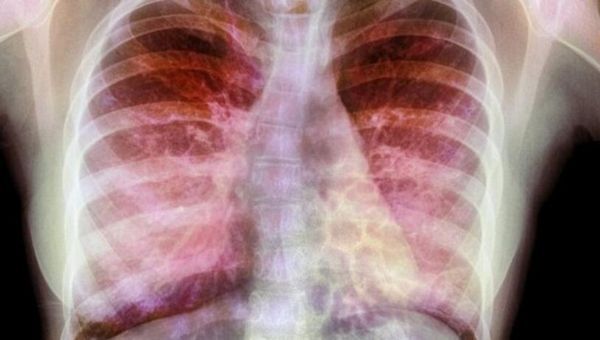

文章中,研究者解释了为何囊性纤维化患者非常容易患上呼吸道感染,25年前,研究人员就发现CFTR基因的突变会诱发肺部囊性纤维化,CFTR基因能表达产生CFTR蛋白帮助在细胞内外运输氯离子,如果没有这种离子运输的话,肺部中的粘液就会越来越粘厚,从而就很容易诱发肺部被细菌感染,尤其是假单胞菌,细菌的感染也会加速机体炎性反应的发生,从而导致持续性难以治疗感染性疾病的发生。

这项研究中,研究者发现,CFTR突变会通过一种完全不同的方式来促进感染进行;研究者Sebastian A. Riquelme博士表示,携带CFTR突变的细胞或许对细菌免疫反应较低,从而就会降低机体清除感染的能力,也会促进炎症扩张;这一点看起来非常有趣,因为其阐明了一种平行的解除管制的免疫学机制,这种机制会促进呼吸道破坏,这种效应远远超过了CFTR对粘液的效应。

当然了,这也是PTEN发挥作用的场所,研究人员并不清楚PTEN如何参与囊性纤维化的发病过程,如今通过对缺失PTEN的小鼠进行研究后研究人员发现小鼠对假单胞菌会产生严重的炎性反应,而且小鼠体内也会表现出像在囊性纤维化患者中出现的清除能力下降的表现。当PTEN位于肺部细胞和免疫细胞表面时,其能帮助有效清除假单胞菌,并且抑制炎症反应,但PTEN似乎只有在吸附到CFTR上才会表现出这样的作用。

在大多数囊性纤维化病例中,很少有CFTR能找到前往细胞表面的路,最后它们往往会失去联系从而让细菌变得更加疯狂。最新开发出的囊性纤维化药物常常会将突变的CFTR推向细胞表面,从而就能改善细胞内外氯离子通道的功能,减少粘液的堆积;本文研究发现“诱骗”无功能的CFTR进入到细胞表面似乎也是有益的,甚至异常的CFTR也能同PTEN协作来抵御机体感染。